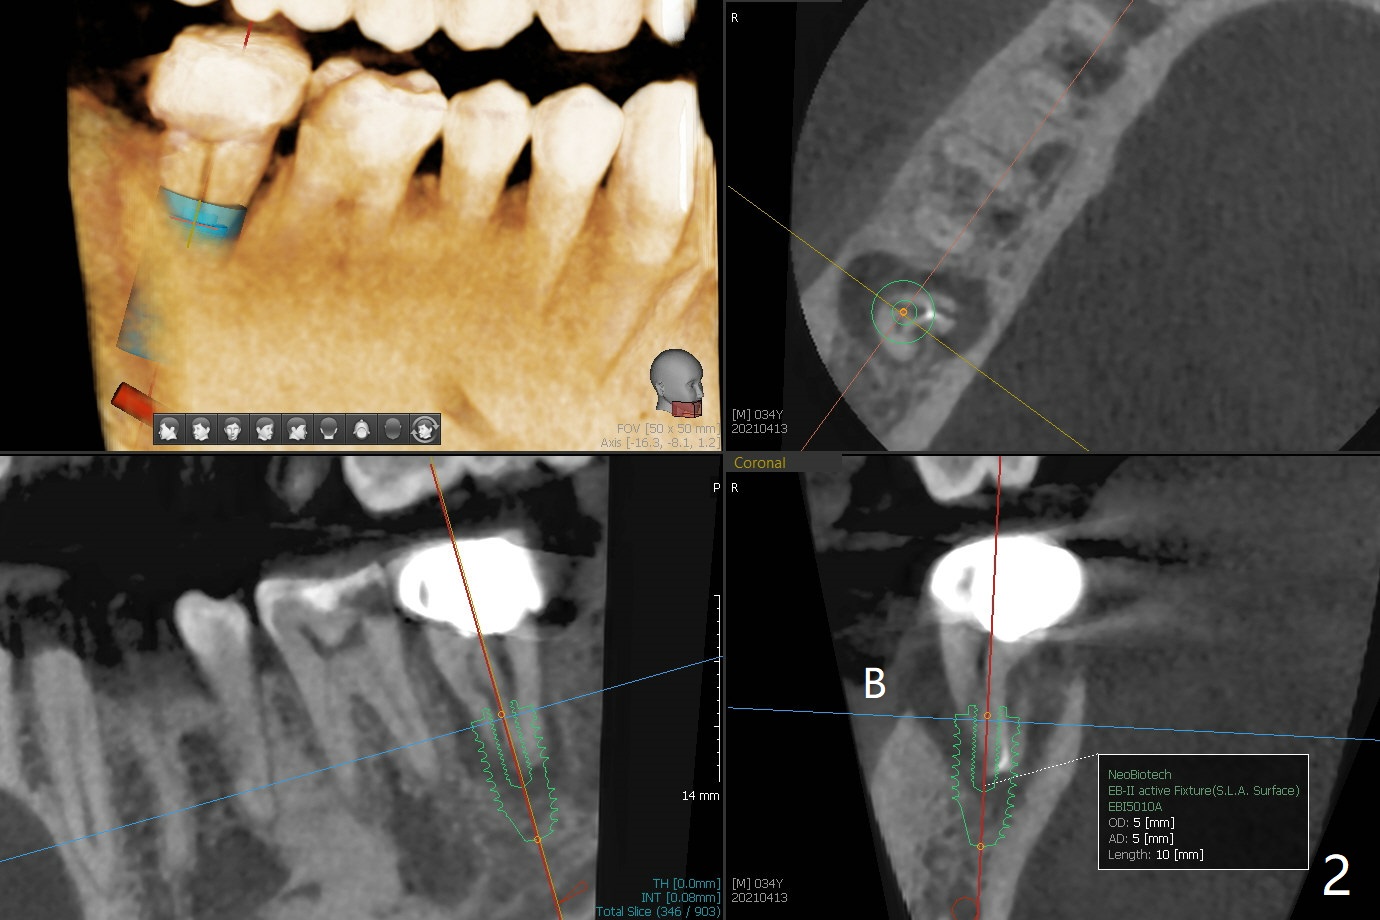

34岁男抱怨右下7根管治疗后牙齿松动,根尖片证实根裂(图一),第二前磨牙和第一磨牙之间有致密骨质(图一:*,图三)。尽管患牙周围骨质吸收严重,尤其是颊侧牙槽嵴(图二:B),必须做即刻种植。植骨有时效果不佳,没有减少手术难度。拖延治疗可能增加对合牙过度萌出,尤其是咬合力大病人。虽然植体颊侧螺纹有暴露危险(图四:>),但是颊侧牙龈附着很长(双箭头),结合基台(图五:粉红色)和临时牙冠(白色),牙龈创造有利的植骨床(红色:骨粉)。